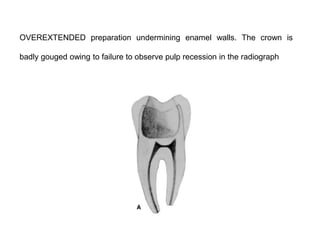

OVEREXTENDED preparation undermining enamel walls. The crown is

badly gouged owing to failure to observe pulp recession in the radiograph